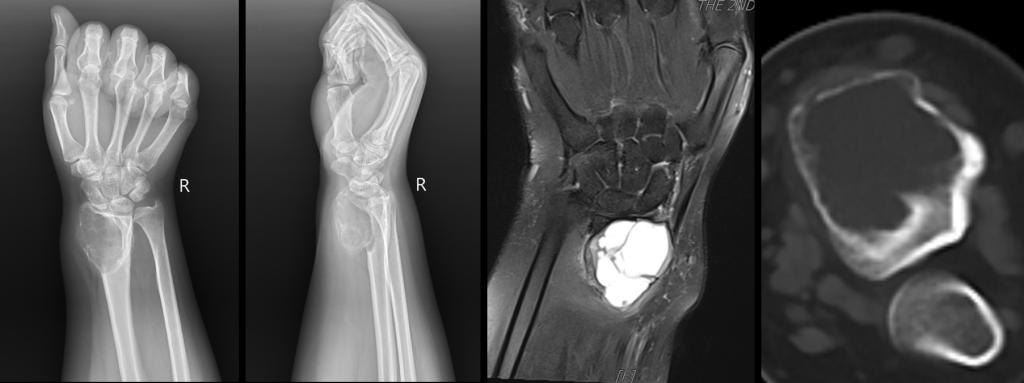

患者党**,28岁女性,因发现右侧腕部肿物伴疼痛1年来我院就诊。赵波副教授团队接诊了该患者,在对患者进行详细的专科查体后,结合患者的主诉、辅助检查结果、既往病史、现病史等综合信息,经穿刺病理活检,确诊其为“桡骨巨细胞瘤,Ⅲ级”。

赵波副教授介绍,骨巨细胞瘤是一种良性的、有局部侵袭性的肿瘤,占骨的原发肿瘤的4%-5%,骨良性肿瘤的22.7%,常表现为疼痛,肿胀,有压痛。对大多数骨巨细胞瘤患者来说,外科手术治疗是目前主要的治疗方法,其中又以病灶扩大刮除、瘤腔灭活、骨水泥填充为主要手术方式。但是该患者骨巨细胞分级达Ⅲ级,肿瘤边界不清、有骨皮质破坏,使用病灶刮除的方法可能无法完整清除病灶,且极有可能进一步破坏皮质骨,导致病理性骨折和肿瘤转移。经过我院骨与软组织肿瘤MDT团队会诊后,决定给予患者3个月的地舒单抗治疗后,采用桡骨远端肿瘤完整切除3D打印桡骨重建的手术。